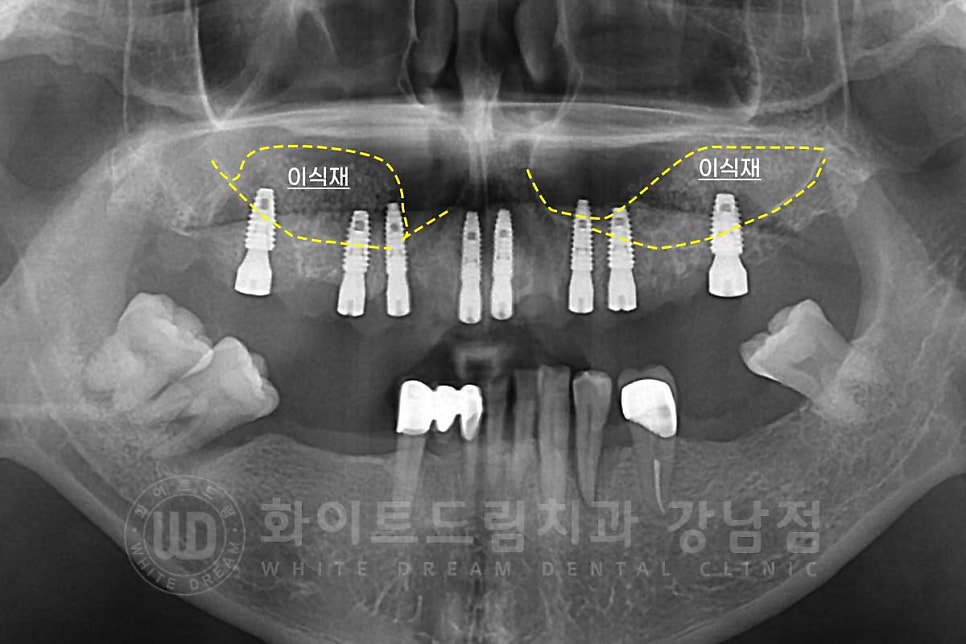

환자분의 상악 수술 후 x-ray 사진입니다.

23.08.12일 날 상악동 거상술을 동반한 14,13,11,21,23,24,26번 임플란트 식립까지

진행한 상태입니다.

치료 후 x-ray 사진입니다.

상악동 막도 잘 올라가고 이식된 뼈들도 새로운 뼈로 잘 만들어진 것이 확인됩니다.